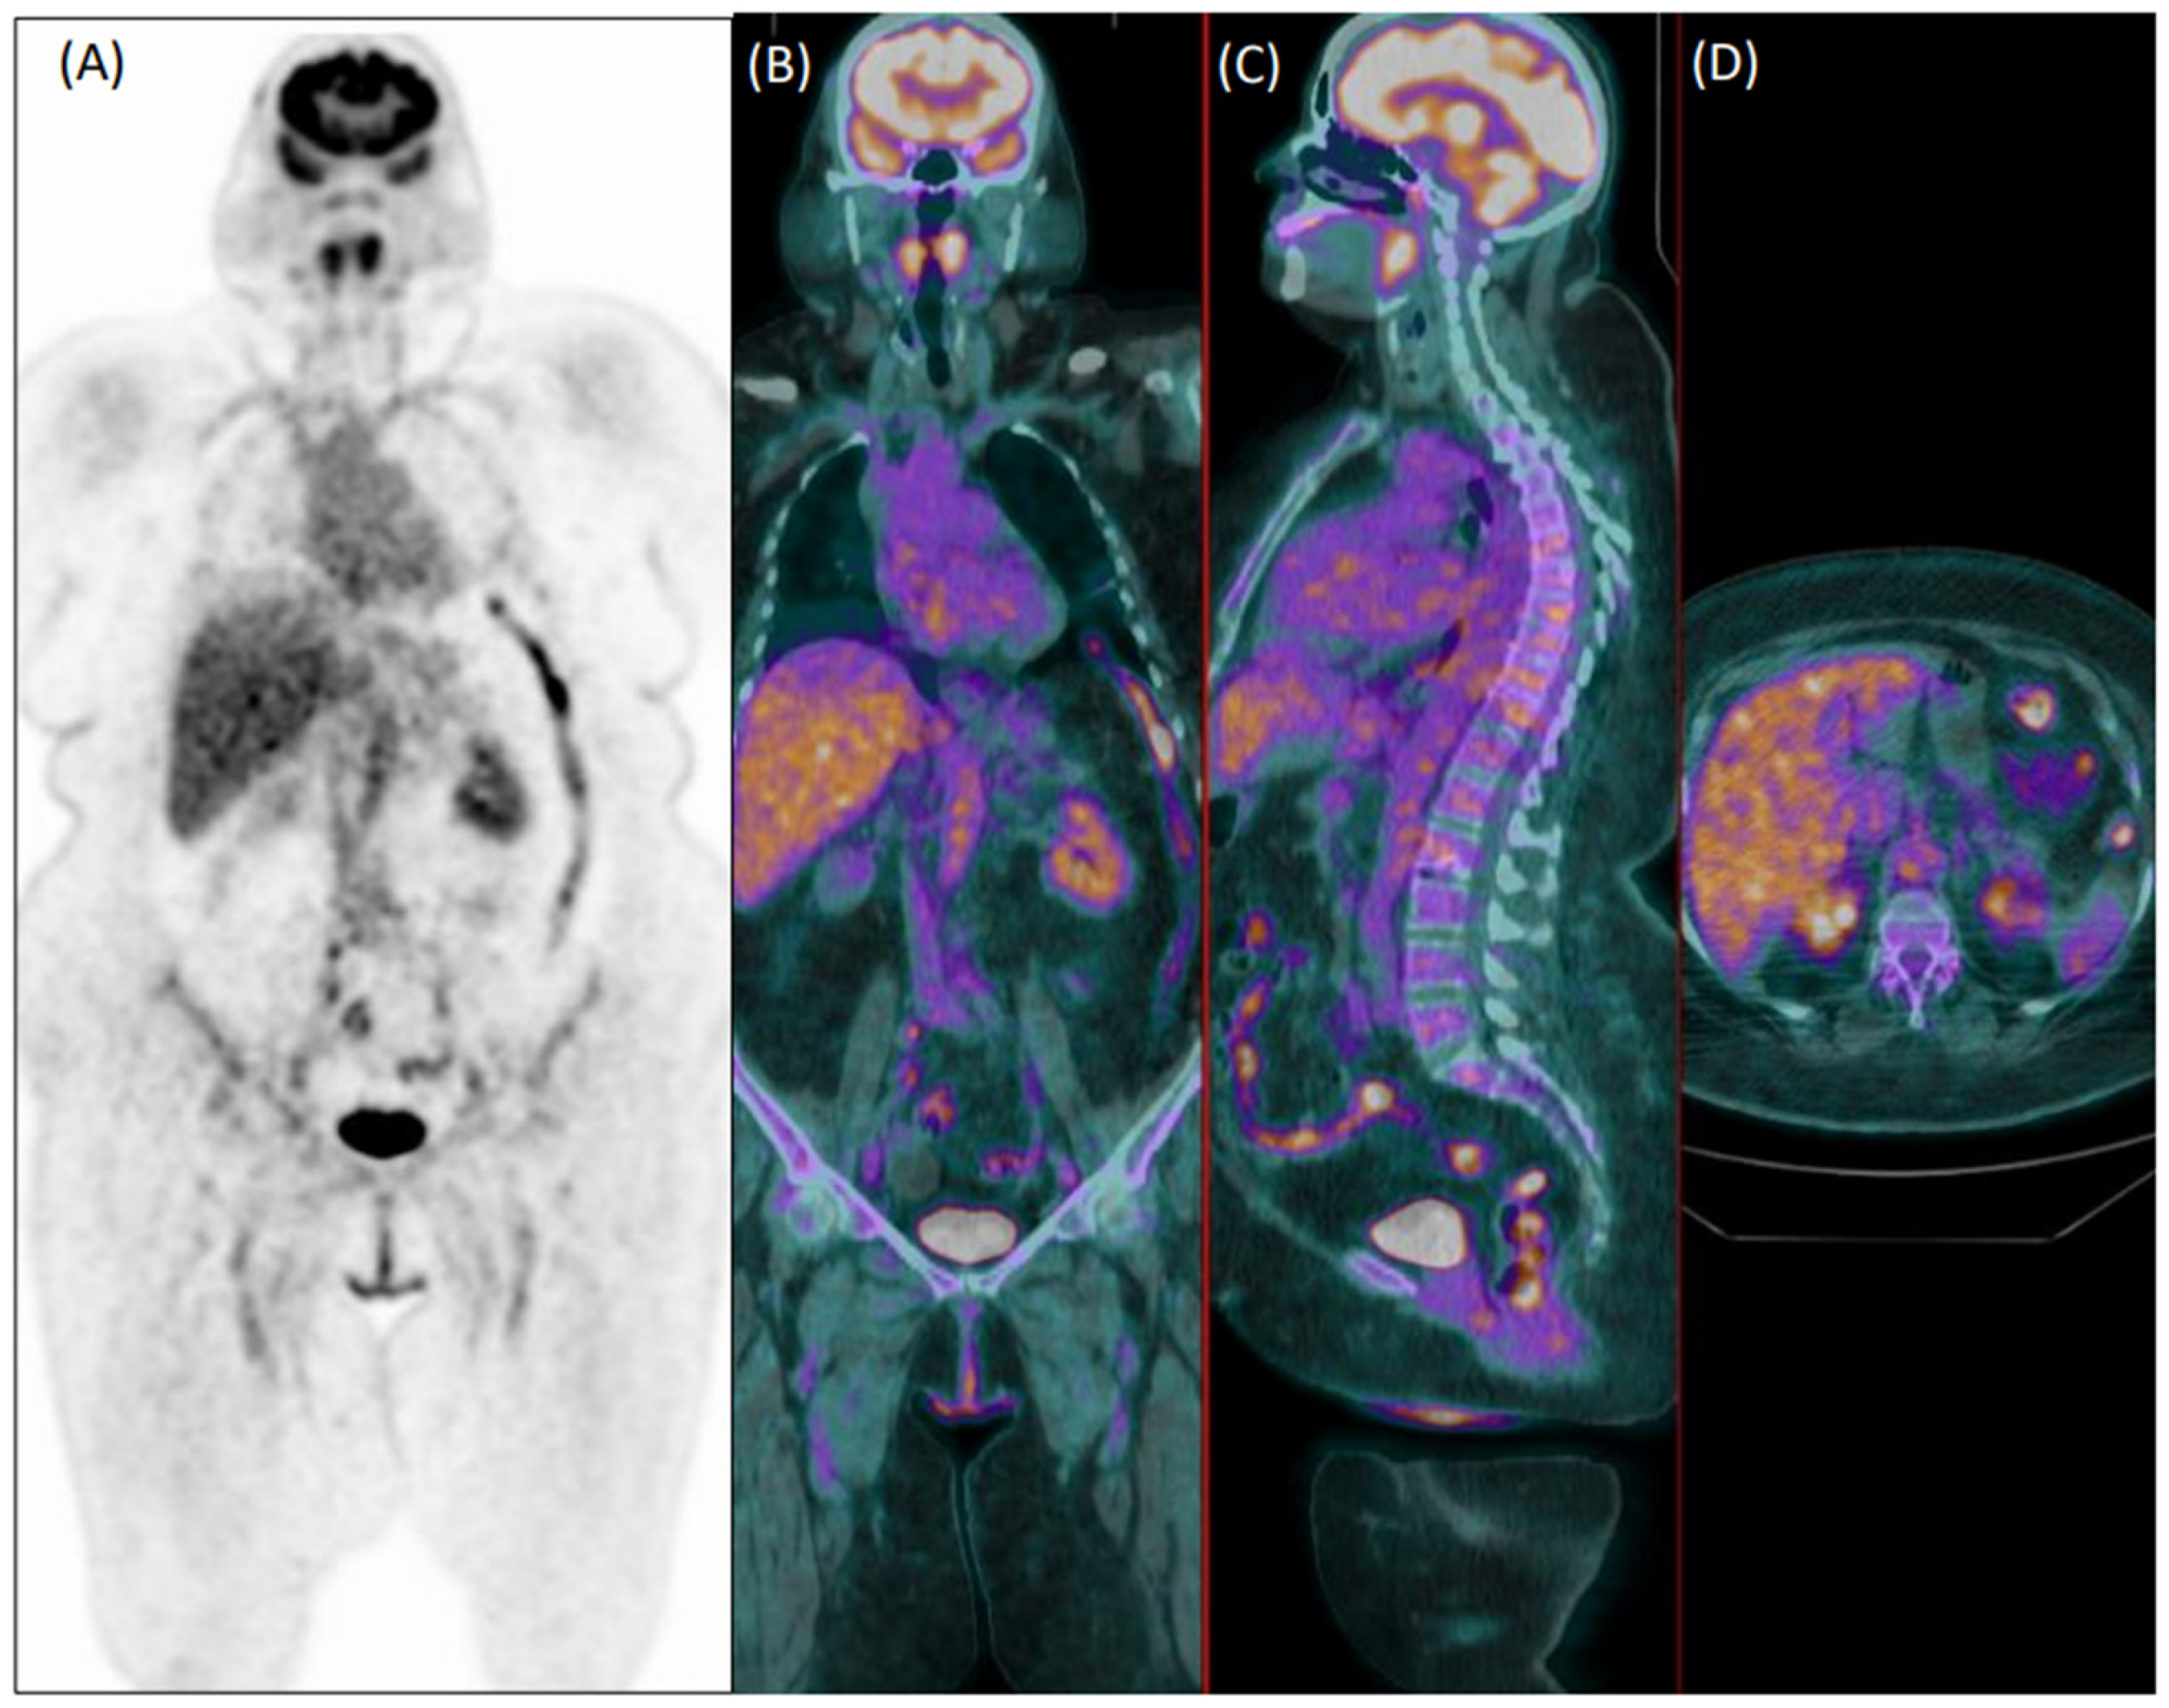

In total, 81 patients (29%) were clinically diagnosed with LVV. Reader 1 and reader 2 failed diagnosis in 76 patients (37 false negative and 39 false positive) and 92 patients, respectively (33 false negative and 59 false positive). Figure 1 and Figure 2 show examples of a true positive and a false positive PET exam. Among the 76 patients wrongly classified by reader 1, 51 were >65-years-old, 44 were overweight, 46 were taking steroids, 12 presented with hyperglycemia, 29 were early acquired, while in 26 patients, the acquisition was delayed, and 23 were scanned with P1.

Figure 2. Coronal [18F]FDG PET (A) and fused PET/CT coronal (B), sagittal (C), and axial (D) images of a 75-year-old female patient with diffuse articular pain and suspicion of vasculitis, not further confirmed during clinical follow-up. Images were evaluated as positive for increased uptake in the aorta, and both subclavian and iliac arteries by the experienced reader 1. Reader 2 evaluated the exam as negative.